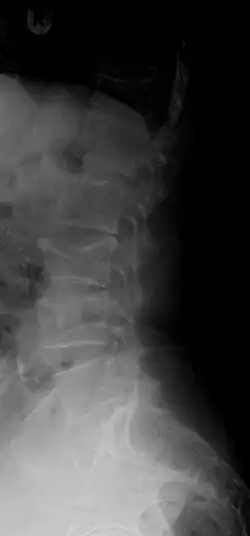

X-ray of the lumbar spine with a compression fracture of the third lumbar vertebra. -